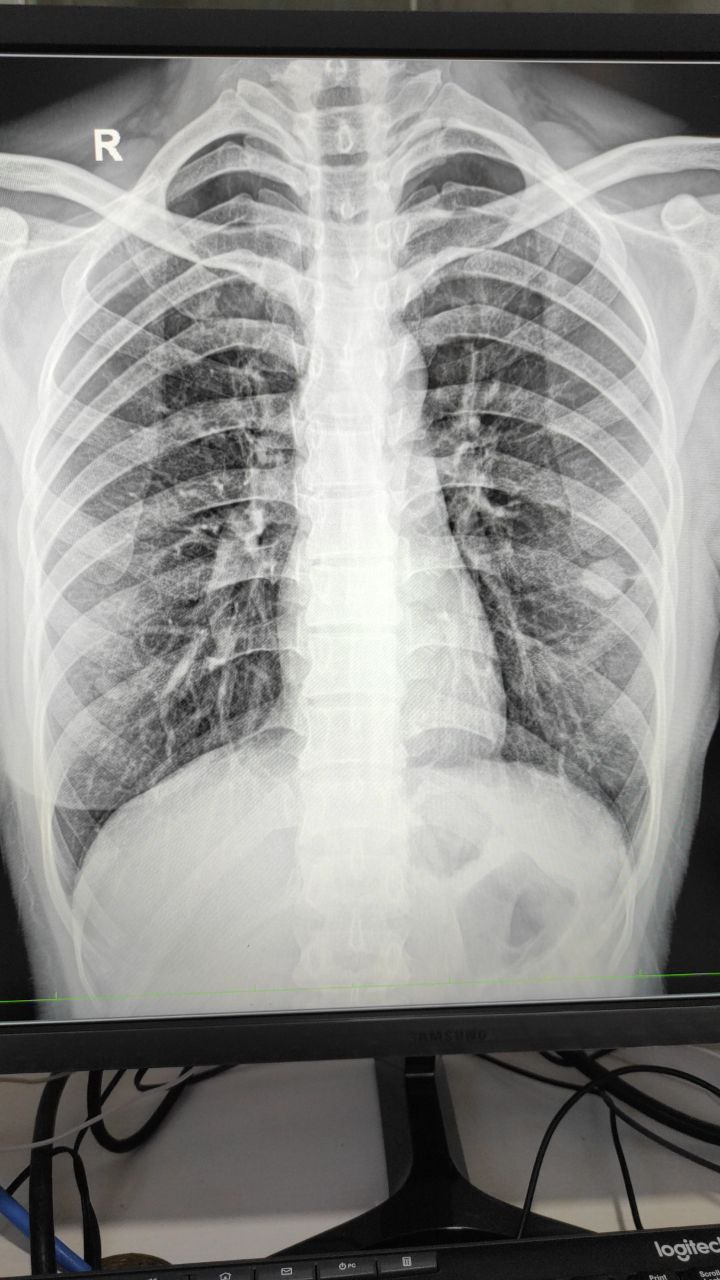

Добрый день. Татьяна. Хотела проконсультироваться по снимку. Обнаружили ковид .вдруг воспаление.. Хотела  уточнить.. Но я так понимаю тут чат для медиков. Уж простите, что внедрилась. Возможно кто-то поможет.